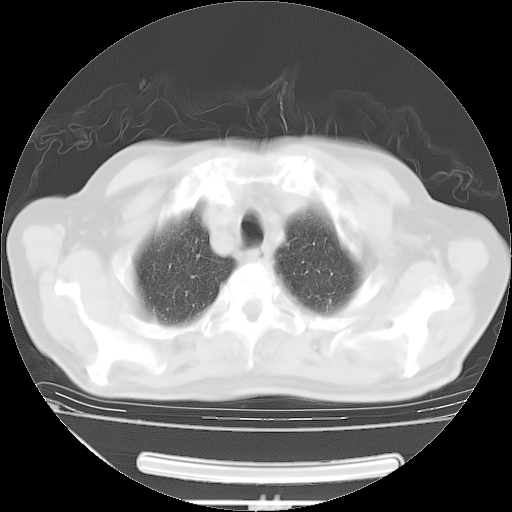

胸腹部CT,诊断意见:左上肺叶钙化灶、左侧胸膜局限性增厚并钙化、胆囊炎。描述部分肺组织呈磨玻璃样改变。